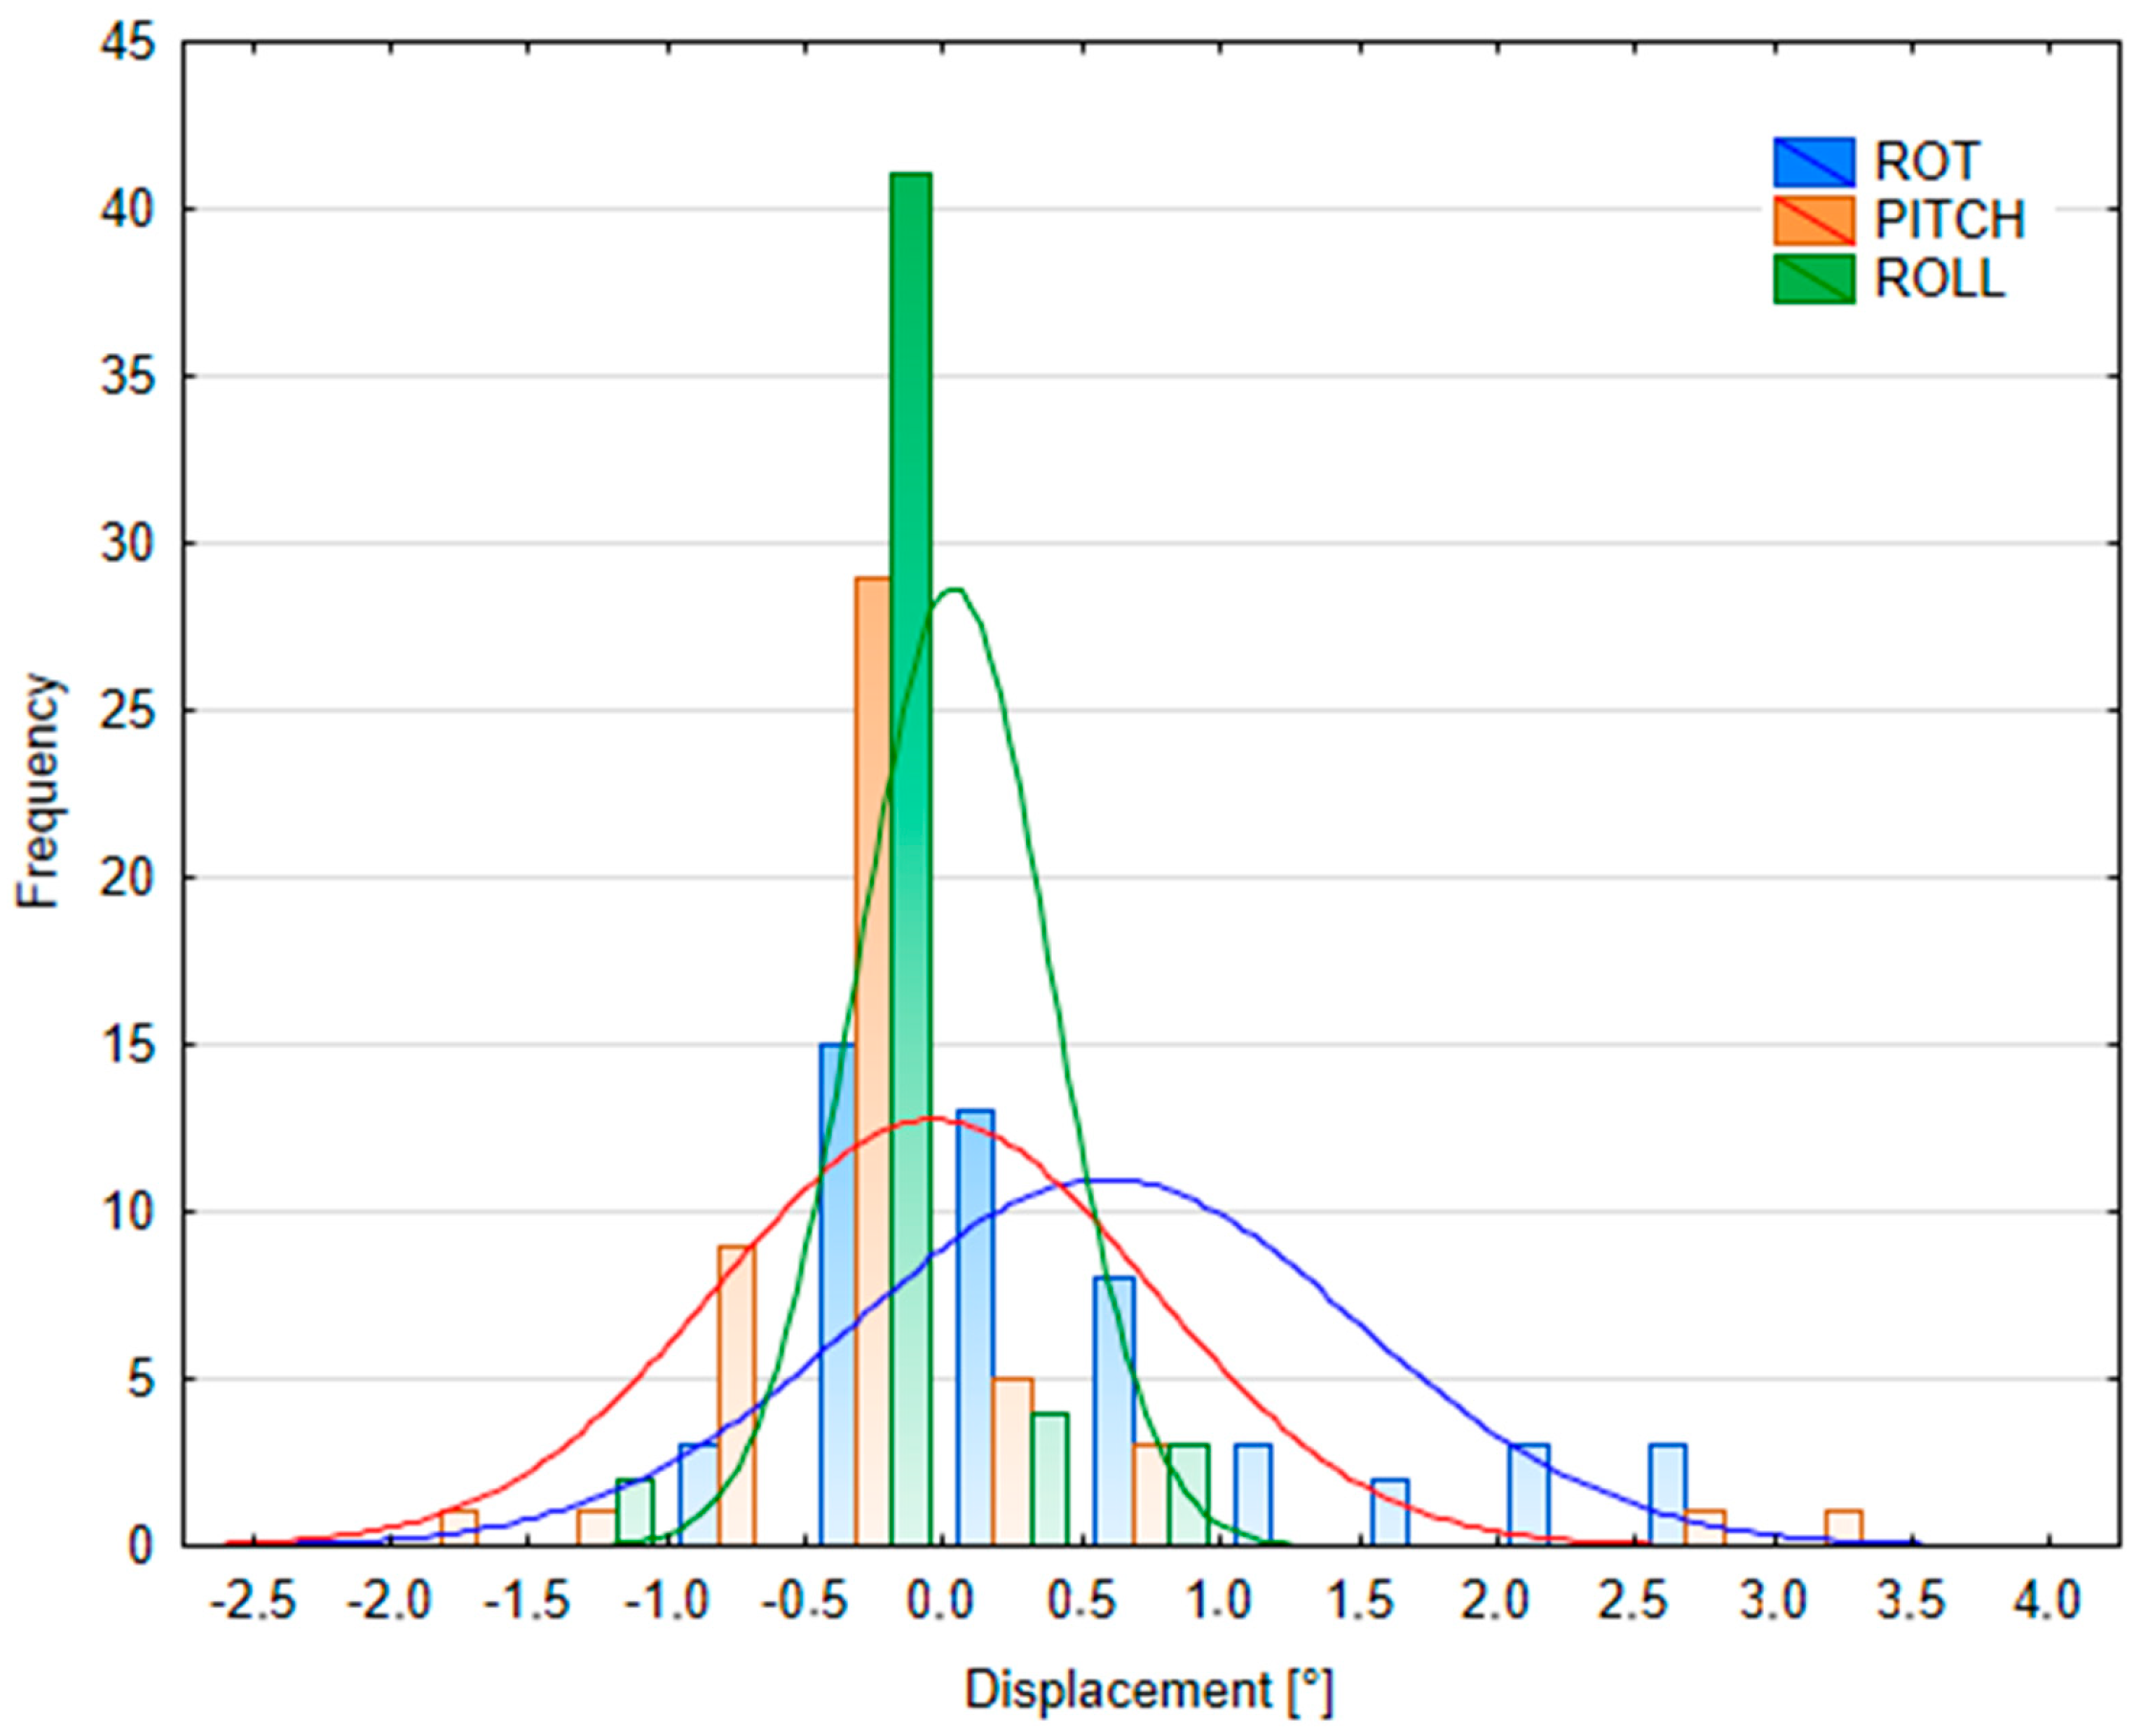

3.2.2. Patient Position Variability

| Table Shift Coordinates | Median kV Portal Imaging Setup Error | Median kV Portal Imaging DIBH Reproducibility | ||||

|---|---|---|---|---|---|---|

| Male (n = 45) | Female (n = 38) | p-Value | Male (n = 17) | Female (n = 33) | p-Value | |

| X (lateral) [cm] | 0 (−0.06; 0.10) | −0.14 (−0.30; 0) | p < 0.05 | 0 (−0.06; 0.03) | −0.09 (−0.34; 0) | p < 0.05 |

| Y (longitudinal) [cm] | 0.02 (−0.14; 0.24) | −0.03 (−0.34; 0.12) | p = 0.16 | 0 (−0.15; 0.06) | −0.07 (−0.45; 0) | p = 0.13 |

| Z (vertical) [cm] | 0 (−0.06; 0.11) | 0.01 (−0.06; 0.12) | p = 0.74 | 0.05 (−0.1; 0.09) | 0.02 (0; 0.12) | p = 0.39 |

| MAG (magnitude) [cm] | 0.34 (0.16; 0.43) | 0.33 (0.17; 0.68) | p = 0.18 | 0 (0; 0.08) | 0 (0; 0.26) | p = 0.06 |

| ROT [°] | 0 (−0.2; 0.4) | 0.65 (0; 1.5) | p < 0.05 | 0 (−0.2; 0.3) | 0.5 (0; 1.5) | p < 0.05 |

| PITCH [°] | −0.31 (−0.93; 0) | −0.05 (−0.3; 0.5) | p < 0.05 | −0.27 (−0.5; 0) | 0 (−0.21; 0.07) | p = 0.11 |

| ROLL [°] | 0 (0; 0) | 0 (0; 0) | p = 0.09 | 0 (0; 0) | 0 (0; 0) | p = 0.43 |

| Tolerances Within | kV Portal Imaging Setup Error (Interfractional, n = 91) | kV Portal Imaging DIBH Reproducibility (Intrafractional, n = 48) | ||||

|---|---|---|---|---|---|---|

| X | Y | Z | X | Y | Z | |

| 1 mm | 45.1% | 34.1% | 50.5% | 45.8% | 41.7% | 56.3% |

| 2 mm | 63.7% | 46.2% | 80.2% | 64.6% | 56.3% | 85.4% |

| 3 mm | 82.4% | 58.2% | 87.9% | 75.0% | 66.7% | 91.7% |

| 4 mm | 90.1% | 74.7% | 93.4% | 83.3% | 75.0% | 93.8% |

| 5 mm | 96.7% | 82.4% | 97.8% | 93.8% | 85.4% | 93.8% |